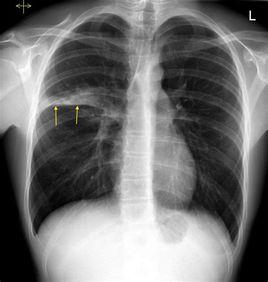

2.X線胸片正常;